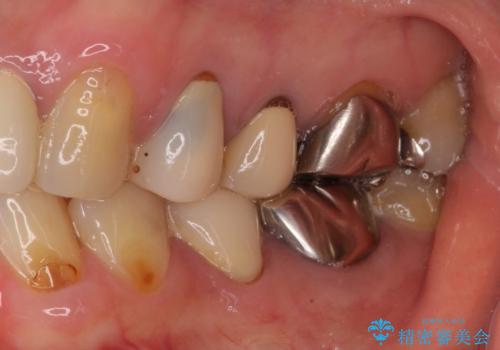

奥歯を中心に銀歯が多く装着されており、一部の歯は咬合時に痛みを感じている状態でした。

必要な歯に根管治療を行い、オールセラミッククラウンにて補綴治療を行うこととしました。

一部根管治療では症状が改善しなかったため、歯根端切除術を行いました。